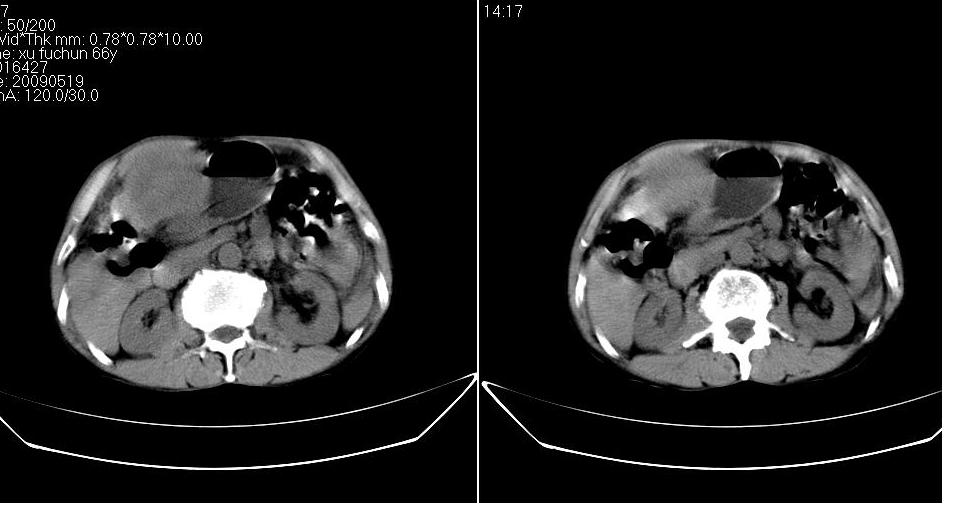

标题: CT20033:上腹部CT平扫

男 66岁,腹疼,b超提示考虑肝癌。

考虑巨块型型肝癌坏死、出血。建议增强。

考虑巨块型型肝癌,建议行进一步检查,如增强、afp检查。

考虑肝左叶巨块型肝癌可能性大;建议行增强ct扫描。